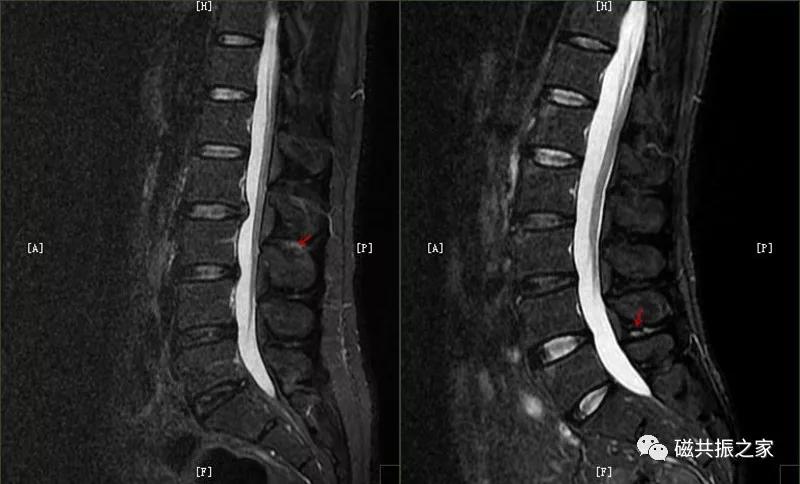

8.椎体骨折

椎体压缩性骨折常成前窄后宽的楔形改变,新鲜骨折(红箭头)常在T1WI呈低信号(出血时可呈高信号),T2WI呈低、中信号,在脂肪抑制的T2WI上呈高信号。椎体陈旧性骨折(白箭头)信号类似于正常椎体信号。如需了解脊柱骨折分型请查阅脊柱骨折的分型。